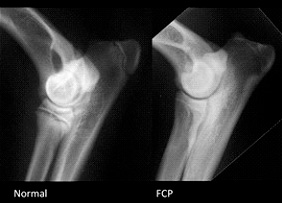

La Displasia del gomito:

La displasia del gomito (ED - Elbow Dysplasia) è una malattia scheletrica che colpisce l'articolazione del gomito e indica uno sviluppo anomalo dell'articolazione del gomito che porta ai fenomeni artritici, artrosici e al distacco di frammenti ossei. Con il termine "displasia del gomito" (ED) s’intende un insieme di patologie a carico dell'articolazione omero-radio-ulnare.

Le condizioni patologiche sono: FCP - Frammentazione del processo coronoideo mediale dell'ulna OCD - Osteocondrite dissecante del comparto mediale del condilo omerale UAP - Mancata unione del processo anconeo dell'ulna INC - Incongruenza dell'articolazione omero-radio-ulnare UME - Mancata fusione del condilo mediale dell'omero IOHC - Ossificazione incompleta del condilo omerale Una crescita asincrona di radio e ulna determina un’incongruenza articolare provocando dei traumi e delle alterazioni sui processi di ossificazione encondrale a livello di cartilagini di accrescimento e articolari. I sintomi di un soggetto colpito dalla displasia del gomito sono vari, si va da una zoppia dell'arto interessato più o meno accentuata con un movimento del gomito aperto verso l'esterno, e nei casi più gravi ad una immobilità dell'arto interessato. Nel 1989 si è costituito l'IEWG (International Elbow Working Group) che si è assunto il compito di identificare, definire e classificare gli aspetti patogenetici e le manifestazioni cliniche della displasia del gomito. Classificazione FCI della displasia del gomito: Salute Rhodesian 8 La displasia del gomito si presenta solitamente in forma bilaterale e si può rilevare una o due o più condizioni insieme. Le razze più colpite e le loro lesioni specifiche sono: Rottweiler, Bovaro del Bernese, Golden Retriever, Pastore Tedesco e Labrador Retriever, tuttavia numerose altre razze sono interessate da questa patologia e anche il Rhodesian Ridgeback, seppur in minor percentuale può essere interessato dalla displasia del gomito.